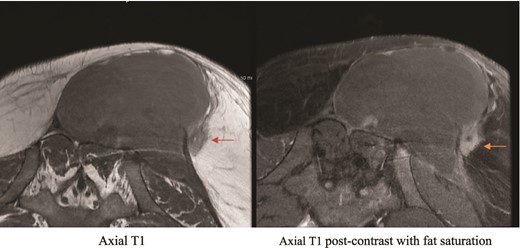

Private hospital MRI. Axial T1 MRI (left) shows left rounded low T2 signal intensity lesion (orange arrow), which shows hyperenhancement (green arrow) on axial T1 fat saturated postcontrast images (right).